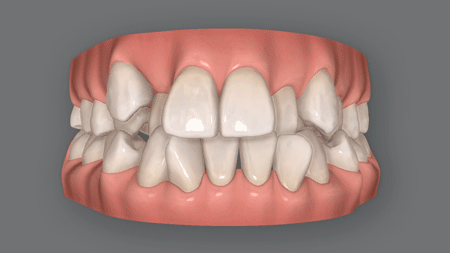

(上記はイメージ画像です)

八重歯が治っても、スペース不足で

口ゴボになってしまう

八重歯の原因がスペース不足なら、そのスペース確保が治療の第一歩。

しかし、前歯しか動かせない格安矯正ではスペースを十分に確保できないので、前歯を外側広げて治療を行います。

この治療法では八重歯は治るかもしれませんが、治療が終わると口元が全体的に前に出てきてしまいます。

つまり、八重歯は治ったとしても、口ゴボという新たな問題が起きてしまうのです。